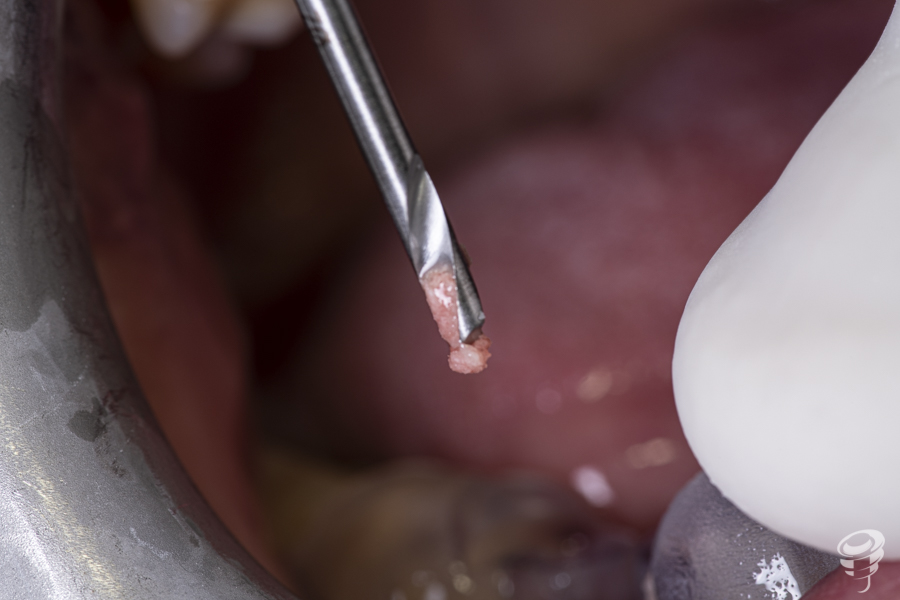

A posteriori, se retira la guía quirúrgica y se realiza el fresado con la fresa Stop de 2 mm de diámetro y 14 mm de longitud directamente sobre los lechos implantarios. Esta fresa creará el lecho implantario idóneo (2 mm infra óseo) ya que el espesor mucoso en este caso es de 2mm.

Secuencia con osteótomos

Tras la realización del fresado anterior, la secuencia siguiente consiste en la introducción progresiva de los osteótomos de menor a mayor diámetro (1 y 2), hasta conseguir la expansión y compactación ósea necesarias para la inserción de los implantes planificados.